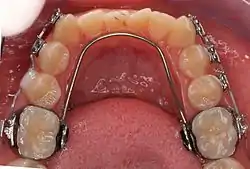

Lingual arch

A lingual arch is an orthodontic device which connects two molars in the upper or lower dental arch. The lower lingual arch (LLA) has an archwire adapted to the lingual side of the lower teeth. In the upper arch the archwire is usually connecting the two molars passing through the palatal vault, and is commonly referred as "Transpalatal Arch" (TPA). The TPA was originally described by Robert Goshgarian in 1972. TPAs could possibly be used for maintaining transverse arch widths, anchorage in extraction case, prevent buccal tipping of molars during Burstonian segmented arch mechanics, transverse anchorage and space maintenance.

LLA and TPA are fabricated by placing bands on the molars. These are connected to the archwire. The wire can be soldered to the bands or inserted into lingual sheaths welded to the molar band (removable LLA and TPA).